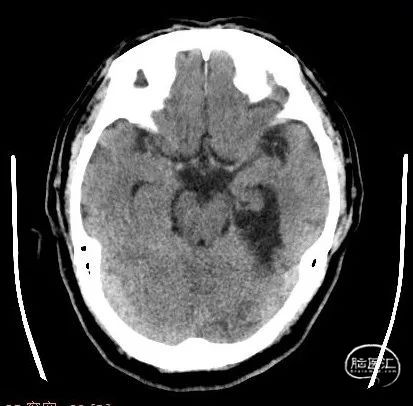

CT检查:

进行了常规化验,颈部超声检查、头部CT和MRI检查。

术后即刻CT:延髓幕上池及大脑纵裂池高密度影。

术后24小时CT复查:左侧小脑新发脑梗死。